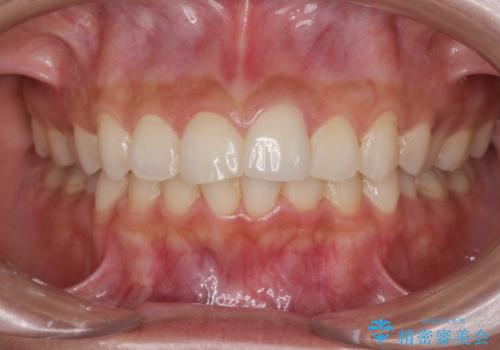

すり減った前歯の形態回復

- すり減ってしまった前歯の審美性の回復を希望され来院されました。

何度かレジン修復を試みたものの、脱離しやすく変色も気になる、とのことでセラミッククラウンによる審美性の回復を計画します。

右側は、クラウンにせず可及的に形態を整えることのみでの対応としました。

自然な色調のセラミッククラウンで審美性を回復することができ、大変満足いただけました。